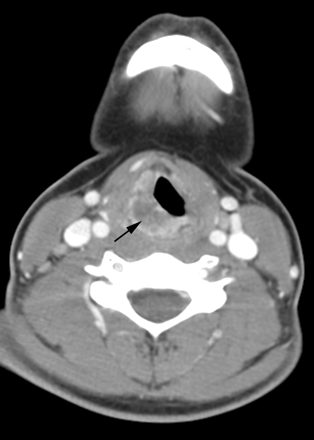

A 14-year-old adolescent girl presented with a 4-month history of hoarseness and sore throat and a 1-month history of odynophagia and dysphagia. Clinical examination revealed a mass at the level of the glottis on the right. Contrast-enhanced CT scan (Fig 2) and MR imaging revealed a 28-mm × 13-mm × 31-mm irregular and heterogeneously enhancing, submucosal mass involving the right side of the epiglottis and aryepiglottic fold, extending inferiorly to involve the right side of the larynx. The mass exhibited a relatively short T2 relaxation time but was hyperintense relative to muscle, with the pulse parameters used on the FSEIR images. There were mildly asymmetric, enhancing ipsilateral level IV and V lymph nodes that did not meet size criteria for pathologic enlargement. On fiberoptic examination, the mass appeared to be bulging into the right pyriform sinus, causing fixation of the right vocal cord, with minimal subglottic extension. Results of biopsy revealed a well-differentiated invasive squamous carcinoma. The tumor was classified as T3N0M0. Fresh tissue was not submitted for karyotypic analysis; results of paraffin-embedded tissue was negative by FISH for t(15;19). In situ hybridization for EBER was not performed.

Patient 2. Carcinoma of the larynx. Contrast-enhanced CT scan of the neck demonstrates an irregular and heterogeneously enhancing, off-midline submucosal mass (arrow) involving the right side of the larynx.